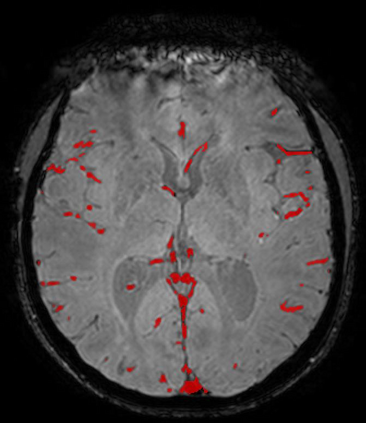

The use of deep learning techniques for 3D brain vessel image segmentation has not been as widespread as for the segmentation of other organs and tissues. This can be explained by two factors. First, deep learning techniques tend to show poor performances at the segmentation of relatively small objects compared to the size of the full image. Second, due to the complexity of vascular trees and the small size of vessels, it is challenging to obtain the amount of annotated training data typically needed by deep learning methods. To address these problems, we propose a novel annotation-efficient deep learning vessel segmentation framework. The framework avoids pixel-wise annotations, only requiring patch-level labels to discriminate between vessel and non-vessel 2D patches in the training set, in a setup similar to the CAPTCHAs used to differentiate humans from bots in web applications. The user-provided annotations are used for two tasks: 1) to automatically generate pixel-wise labels for vessels and background in each patch, which are used to train a segmentation network, and 2) to train a classifier network. The classifier network allows to generate additional weak patch labels, further reducing the annotation burden, and it acts as a noise filter for poor quality images. We use this framework for the segmentation of the cerebrovascular tree in Time-of-Flight angiography (TOF) and Susceptibility-Weighted Images (SWI). The results show that the framework achieves state-of-the-art accuracy, while reducing the annotation time by up to 80% with respect to learning-based segmentation methods using pixel-wise labels for training